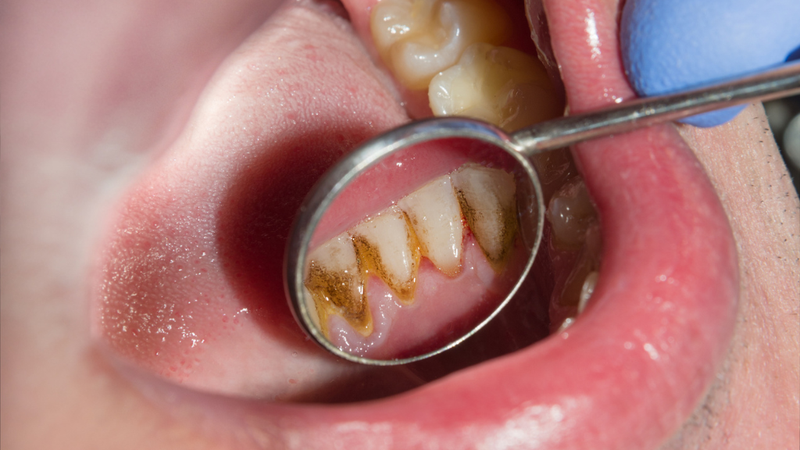

Cao răng hay vôi răng là những mảng bám cứng bám chặt trên bề mặt răng, có thể xuất hiện ở phía trên hoặc dưới đường viền nướu. Khi cao răng tích tụ tại khu vực này, chúng tạo môi trường thuận lợi cho vi khuẩn phát triển, khiến mảng bám bám chặt vào răng và khó làm sạch hơn. Lâu dần, điều này có thể dẫn đến các vấn đề răng miệng nghiêm trọng như viêm nướu, sâu răng, viêm nha chu, thậm chí làm răng bị ố vàng. Không chỉ vậy, cao răng còn là một trong những nguyên nhân chính gây ra hơi thở có mùi khó chịu, làm ảnh hưởng đến sự tự tin trong giao tiếp. Vì vậy, có thể khẳng định rằng cao răng là một trong những tác nhân hàng đầu gây hôi miệng.

Cao răng hình thành từ các chất khoáng trong nước bọt và thực phẩm, nên có thể dễ dàng nhận biết bằng mắt thường. Dấu hiệu rõ ràng nhất là khi quan sát trong gương, bạn sẽ thấy dọc theo viền nướu hoặc quanh răng xuất hiện những mảng bám có màu vàng hoặc nâu. Điểm đặc trưng của cao răng là dù đã vệ sinh răng miệng kỹ lưỡng, các mảng bám này vẫn không thể được loại bỏ bằng cách chải răng thông thường.